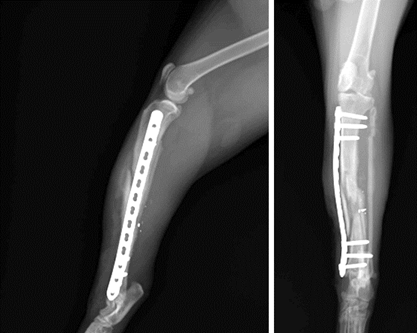

Les radiographies post-opératoires montrent un positionnement très satisfaisant des implants et un réalignement de la fracture (figure 4). Des morceaux de plombs sont cependant encore visualisés.

Figure 4 : Ostéosynthèse après la chirurgie